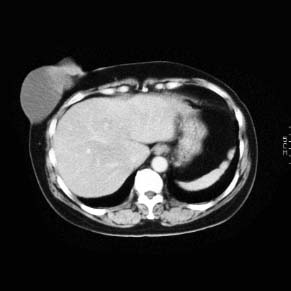

CaseKH02

- Age/Sex: 48F

- Chief Complaint: 乳房腫瘤

- Clinical Course:

- Lab. Data:

- Images:

- CT(1)

CT(2)

CT(2)

- CT(3)

CT(4)

CT(4)

- DSA1

- DSA2